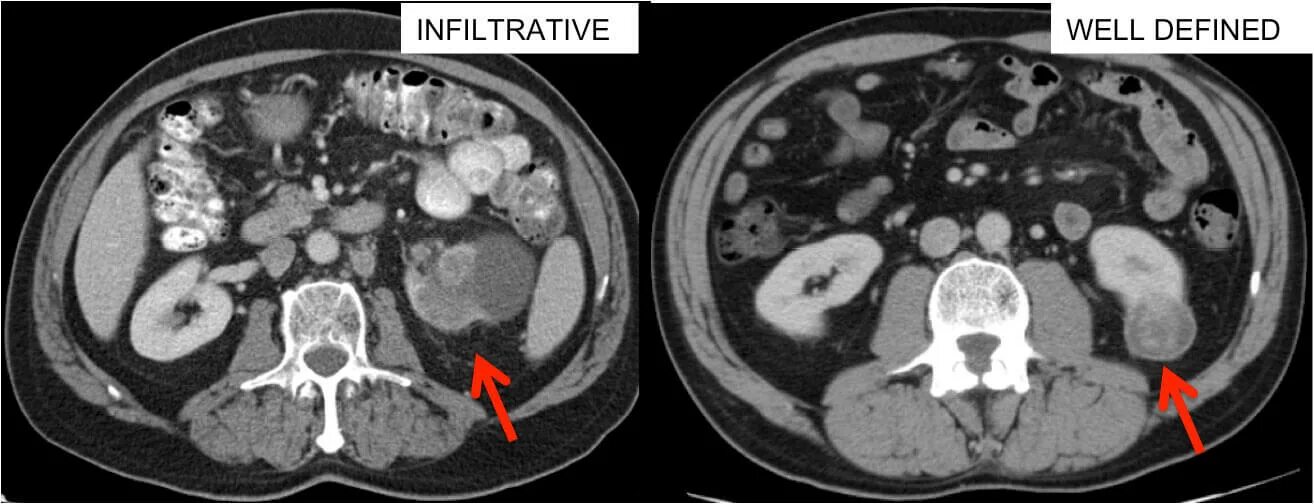

The images be scan